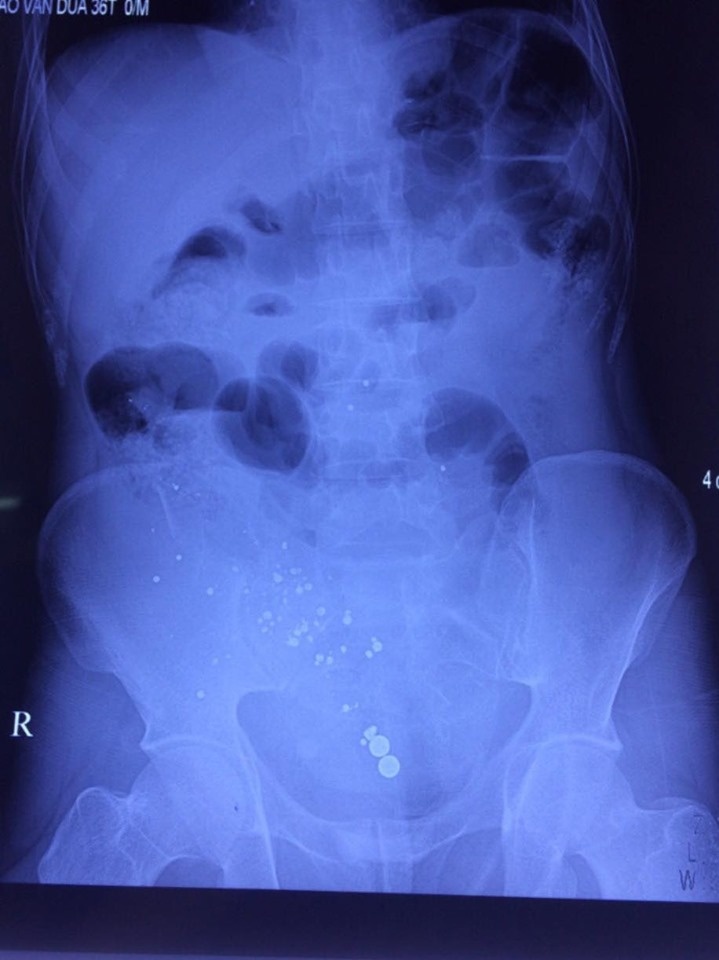

| Phim chụp vùng bụng của bệnh nhân Đ. |

Trên phim chụp cho thấy có nhiều dị vật cản quang ở trong ổ bụng, chẩn đoán vết thương thấu bụng do hỏa khí. Ngay sau đó các bác sĩ đã tiến hành phẫu thuật cho bệnh nhân này.

“Khi phẫu thuật, chúng tôi phát hiện trong bụng bệnh nhân có 2 lít nước máu và tiểu. Niệu quản bị tổn thương nặng nên gây chảy máu và nước tiểu vào ổ bụng. Rất may bệnh nhân không bị thủng ruột”, bác sĩ Quân cho biết.